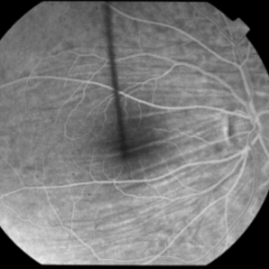

This 53-year-old man was noted to have choroidal folds right greater than left. The visual acuity was normal at 20/15. The choroidal folds are visible on OCT, especially on the vertical cuts that image across the horizontal folds. Angiography revealed staining of the folds without CNVM, choroidal mass, or optic nerve edema.

Condition/keywords: bilateral chorioretinal folds, choroidal folds